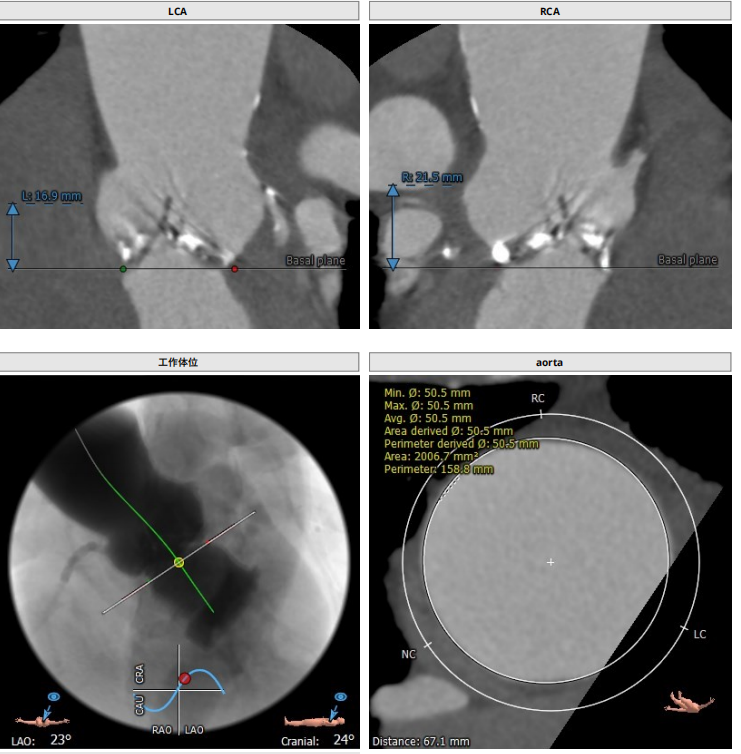

根部解剖

患者为TYPE0二叶瓣,重度钙化,术前可见瓣周突出物,怀疑囊肿,瓣环23.8,LVOT25.5,鱼嘴开口22.8,预计瓣口开口22.3,STJ33.9,窦部空间大,左右冠高度分别为19.9和21.5,预计18号球囊预扩。